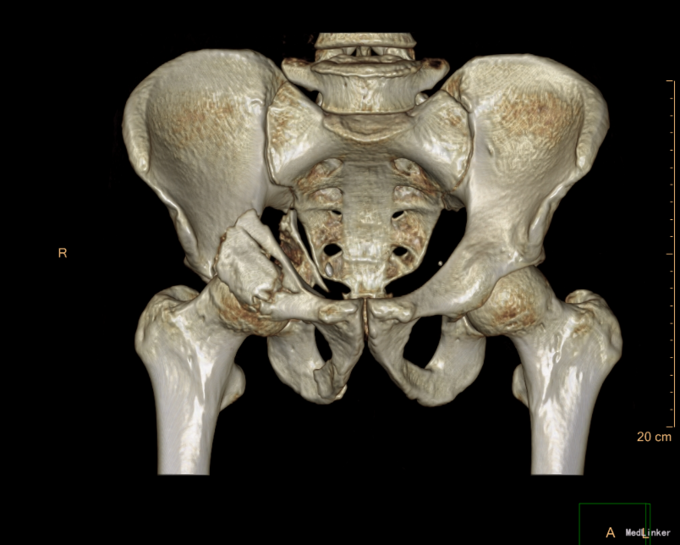

患者于2015年6月10日因车祸摔伤右侧髋关节,出现右髋部疼痛及活动受限。疼痛于活动后加重,休息可稍缓解。后就诊于营口市中心医院行骨盆三维CT示“右髋臼粉碎性骨折”,建议手术治疗,给予胫骨结节骨牵引术,患者于6月17日收入我院运动关节科病房,于6月19日转入我科。

患者入院后急诊行右髋关节脱位手法复位术,右胫骨结节骨骼牵引术。术后患者骨骼牵引约8公斤,术后约一星期后择期行右髋关节骨折切开复位钢板内固定书,术后患者病情平稳,术后三天转入当地医院继续治疗。